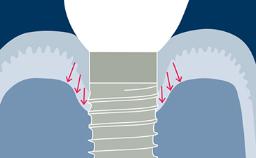

O tratamento com implantes é altamente bem-sucedido, conforme documentado na literatura científica. No entanto, os clínicos devem esperar ver complicações em sua prática diária. As complicações associadas à mucosa ou osso peri-implantar circundante são chamadas de complicações biológicas. Elas ocorrem quando há um desequilíbrio entre o desafio do biofilme bacteriano nos tecidos ao redor do implante e a defesa do hospedeiro, resultando em um processo inflamatório. As complicações biológicas abordadas neste módulo são as doenças peri-implantares, denominadas mucosite peri-implantar e peri-implantite, que podem ocorrer em torno de implantes osseointegrados. Portanto, é importante que o clínico seja capaz de diagnosticar mucosite e peri-implantite peri-implantares e entender as etapas para o manejo dessas complicações.